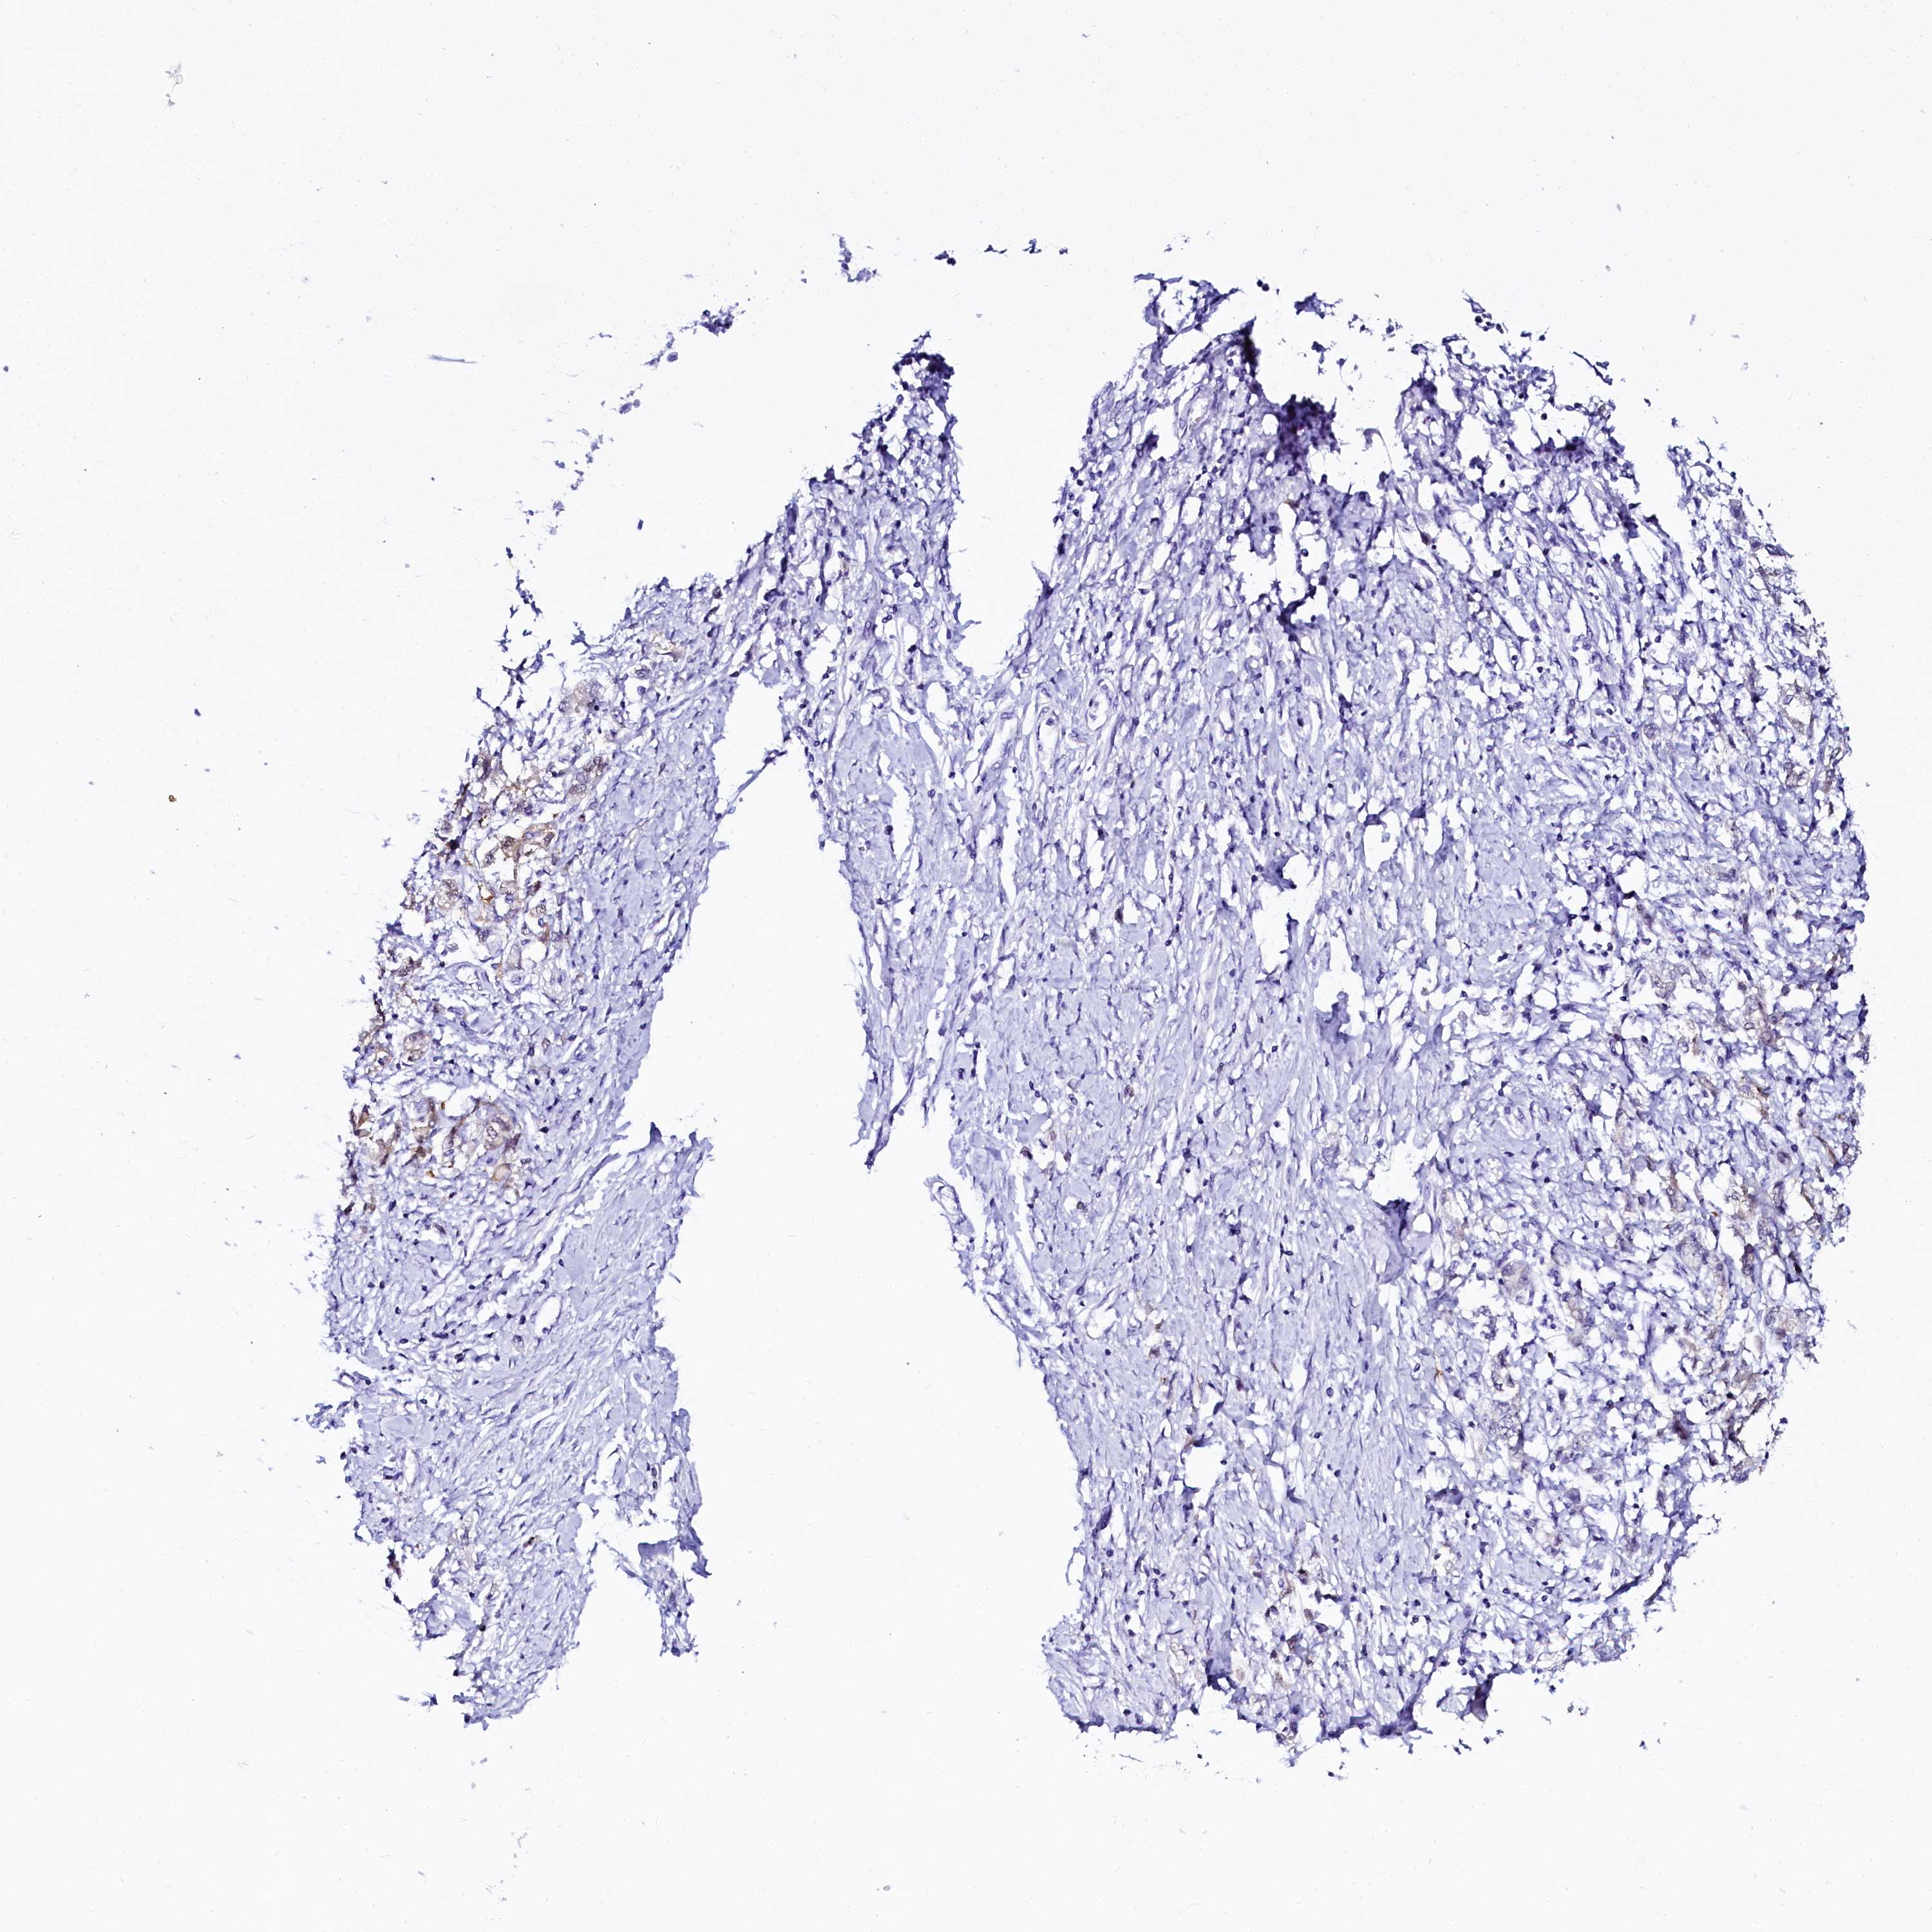

STOMACH CANCER - Protein expressioni

A mouse-over function shows sample information and annotation data. Click on an image to view it in a full screen mode. Samples can be filtered based on level of antibody staining by selecting one or several of the following categories: high, medium, low and not detected. The assay and annotation is described here.

Note that samples used for immunohistochemistry by the Human Protein Atlas do not correspond to samples in the TCGA dataset.

Antibody stainingi

Antibody staining in the annotated cell types in the current human tissue is reported as not detected, low, medium, or high, based on conventional immunohistochemistry profiling in selected tissues. This score is based on the combination of the staining intensity and fraction of stained cells.

Each image is clickable and will lead to virtual microscopy that enables deeper exploration of all samples and also displays staining intensity scores, fraction scores and subcellular localization as well as patient and tissue information for each sample.

Antibody HPA040260

Antibody HPA040621

Staining

High

Medium

Low

Not detected

Intensity

Strong

Moderate

Weak

Negative

Quantity

>75%

75%-25%

<25%

None

Location

Nuclear

Cytoplasmic/membranous

Cytoplasmic/membranous,nuclear

Adenocarcinoma, NOS